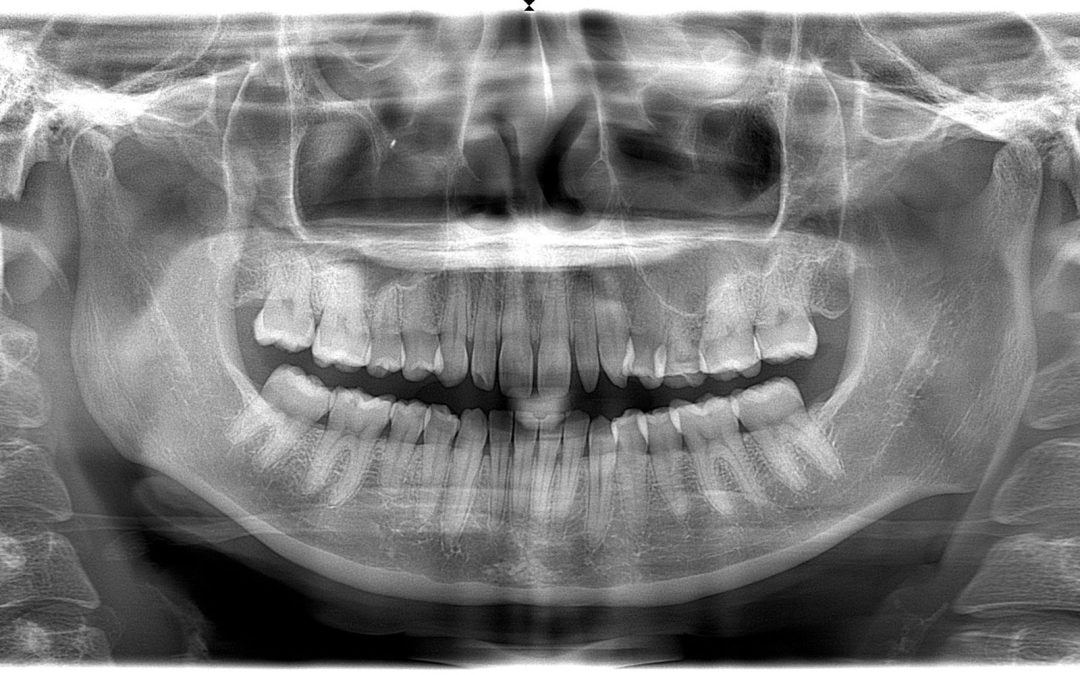

The lateral incisors, also known as the maxillary or upper lateral incisors, appear between the central incisors and our canines. The prominent placement of these teeth makes them an important component of our smile’s appearance. When peg laterals occur, it can make those living with them less willing to smile openly, as they can be a source of embarrassment. There are two known causes of peg laterals, and neither is within the patient’s or dentist’s control to prevent.

The two types of peg laterals are:

- Genetics – Peg laterals appear to run in families, giving them a congenital element.

- Developmental Anomaly – For reasons that are unclear, the adult incisors may not form properly. Another common anomaly is that the adult incisors don’t form at all, resulting in the primary (baby) versions remaining in place.

In both these cases, the result is a smile that has two teeth that don’t match the size of the rest of the teeth. As mentioned before, there are no significant oral health risks to living with peg laterals. One potential health risk is the neighboring teeth moving out of alignment due to the lack of support from normal-sized lateral incisors. Regardless, peg laterals are primarily considered to be a cosmetic concern and are rarely, if ever, covered by dental insurance.